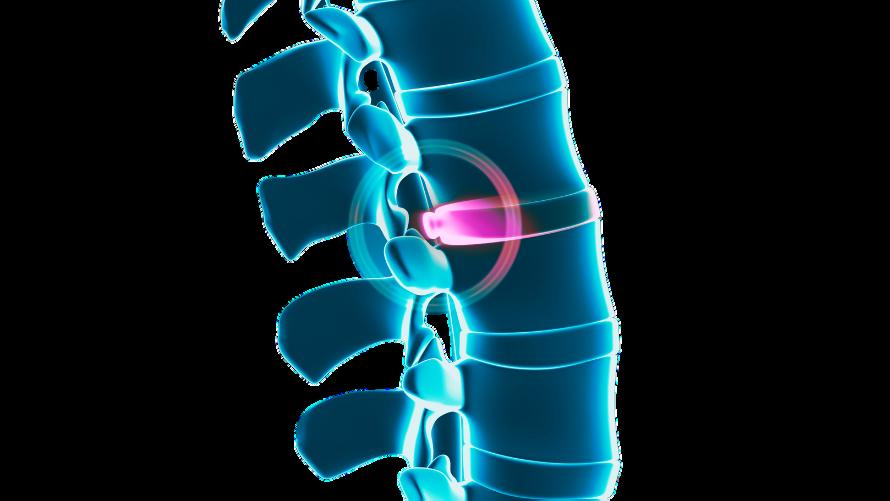

Thereporthastwokeyaims,writtenmostlyto berelevanttoanyonesufferingwithabulging disc,herniateddisc,ruptureddisc,or degenerativediscdisease,thoughitwillalso proveveryusefulandinformativetomany others,andanyonedealingwiththetopicof spinaldiscconditionsitself,